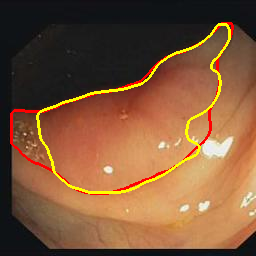

Medical image segmentation is a primary task in many applications, and the accuracy of the segmentation is a necessity. Recently, many deep learning networks derived from U-Net have been extensively used and have achieved notable results. To further improve and refine the performance of U-Net, parallel decoders along with mask prediction decoder have been carried out and have shown significant improvement with additional advantages. In our work, we utilize the advantages of using a combination of contour and distance map as regularizers. In turn, we propose a novel architecture Psi-Net with a single encoder and three parallel decoders, one decoder to learn the mask and other two to learn the auxiliary tasks of contour detection and distance map estimation. The learning of these auxiliary tasks helps in capturing the shape and boundary. We also propose a new joint loss function for the proposed architecture. The loss function consists of a weighted combination of Negative likelihood and Mean Square Error loss. We have used two publicly available datasets: 1) Origa dataset for the task of optic cup and disc segmentation and 2) Endovis segment dataset for the task of polyp segmentation to evaluate our model. We have conducted extensive experiments using our network to show our model gives better results in terms of segmentation, boundary and shape metrics.